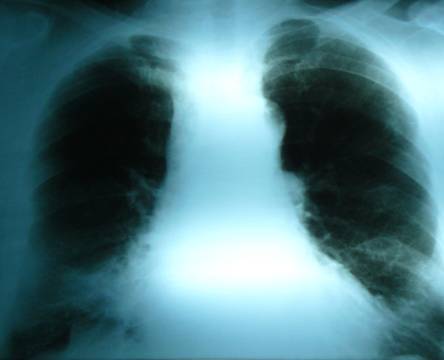

Prezentarea cazului: Bolnav in varsta de 77 ani, de profesie medic veterinar, se interneaza pentru investigarea unui anevrism sacciform la nivelul crosei aortice descoperit intamplator cu ocazia unui consult medical pentru o infectie respiratorie acuta care survine pe fondul unei afectiuni pulmonare preexistente (BPOC). Examenul radiologic cord pulmon a evidentiazat opacitati neomogene in bazele ambelor campuri pulmonare (Fig.1) pentru care se decide explorare computer tomografica care deceleaza anevrism sacciform de crosa aortica. Mentionam ca pacientul este diagnosticat cu cardiomiopatie dilatativa de 5 ani cu disfunctie sistolica severa de VS ( FEVS-30%) probabil tahiaritmica tinand cont de faptul ca prezinta fibrilatie atriala persistenta cu alura ventriculara rapida, in absenta unei medicatii optime. Dintre factorii de risc cardiovascular mentionam dislipidemia, diabetul zaharat tip II si obezitatea .

Figura 1. Radiografie cord-pulmon incidenta postero-anterioara: opacitati pulmonare bazal bilateral, arc aortic dilatat.